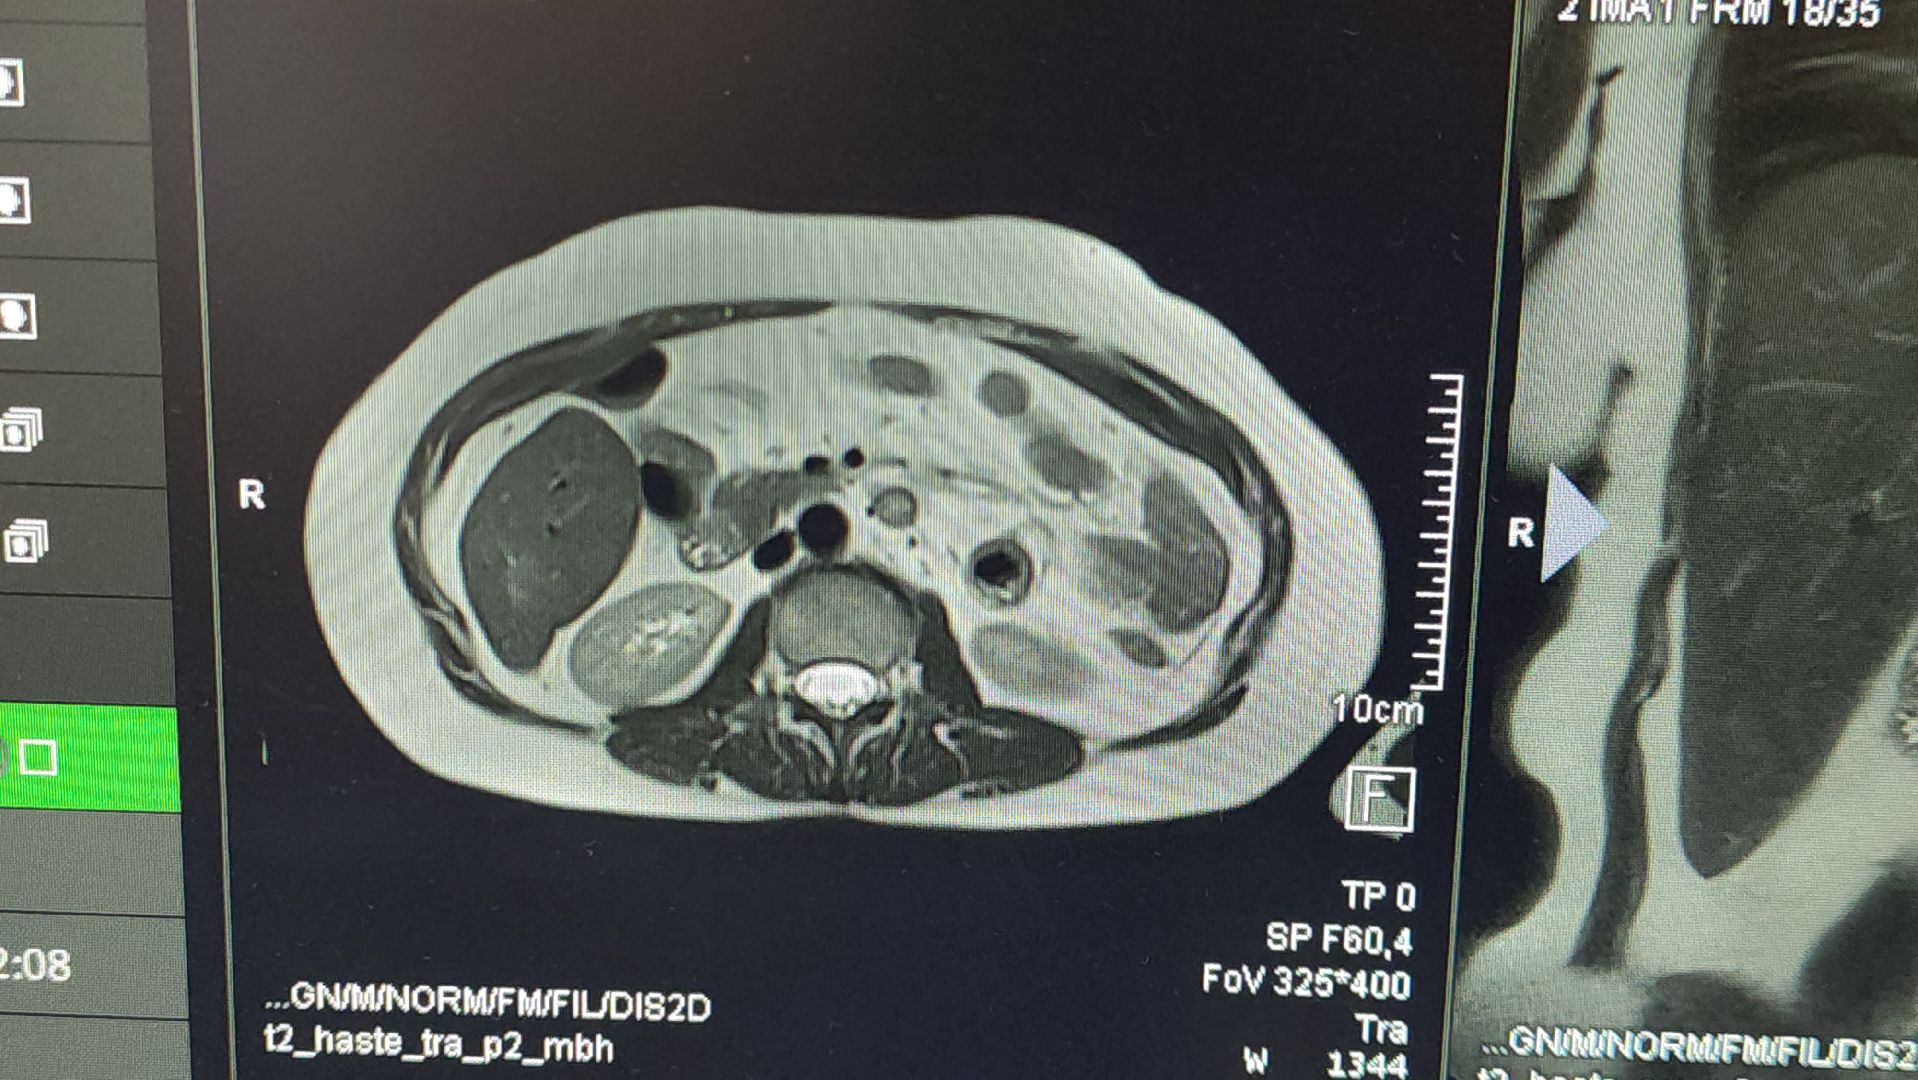

С момента подключения аппарата выполнили 737 исследований. Как отметил Игорь Нараев, в основном это исследования позвоночника и головного мозга, на третьем месте — коленные суставы.